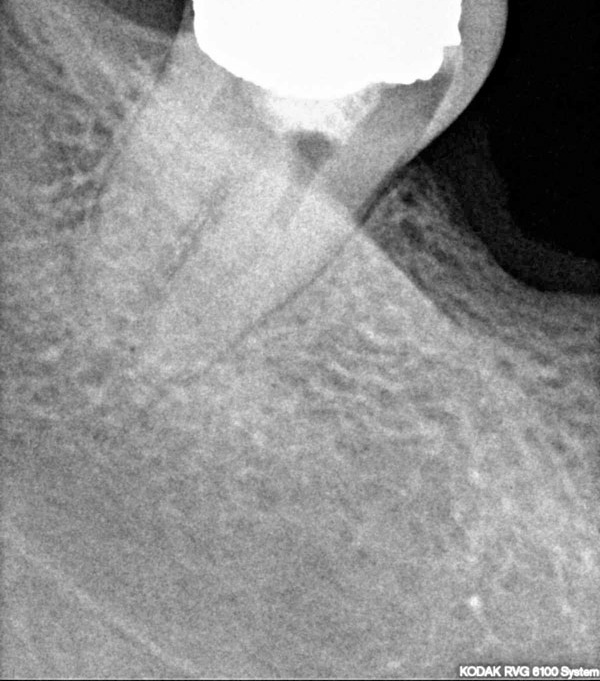

Donji desni umnjak prije i poslije endodontskog liječenja